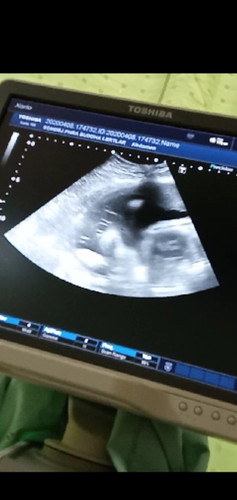

แม่ๆดูออกไหมคะ 33+4

ดูยากกกจุงเบยค่ะ เดาว่าน้องเป็น ผช ^^

ขาหรือเปล่า